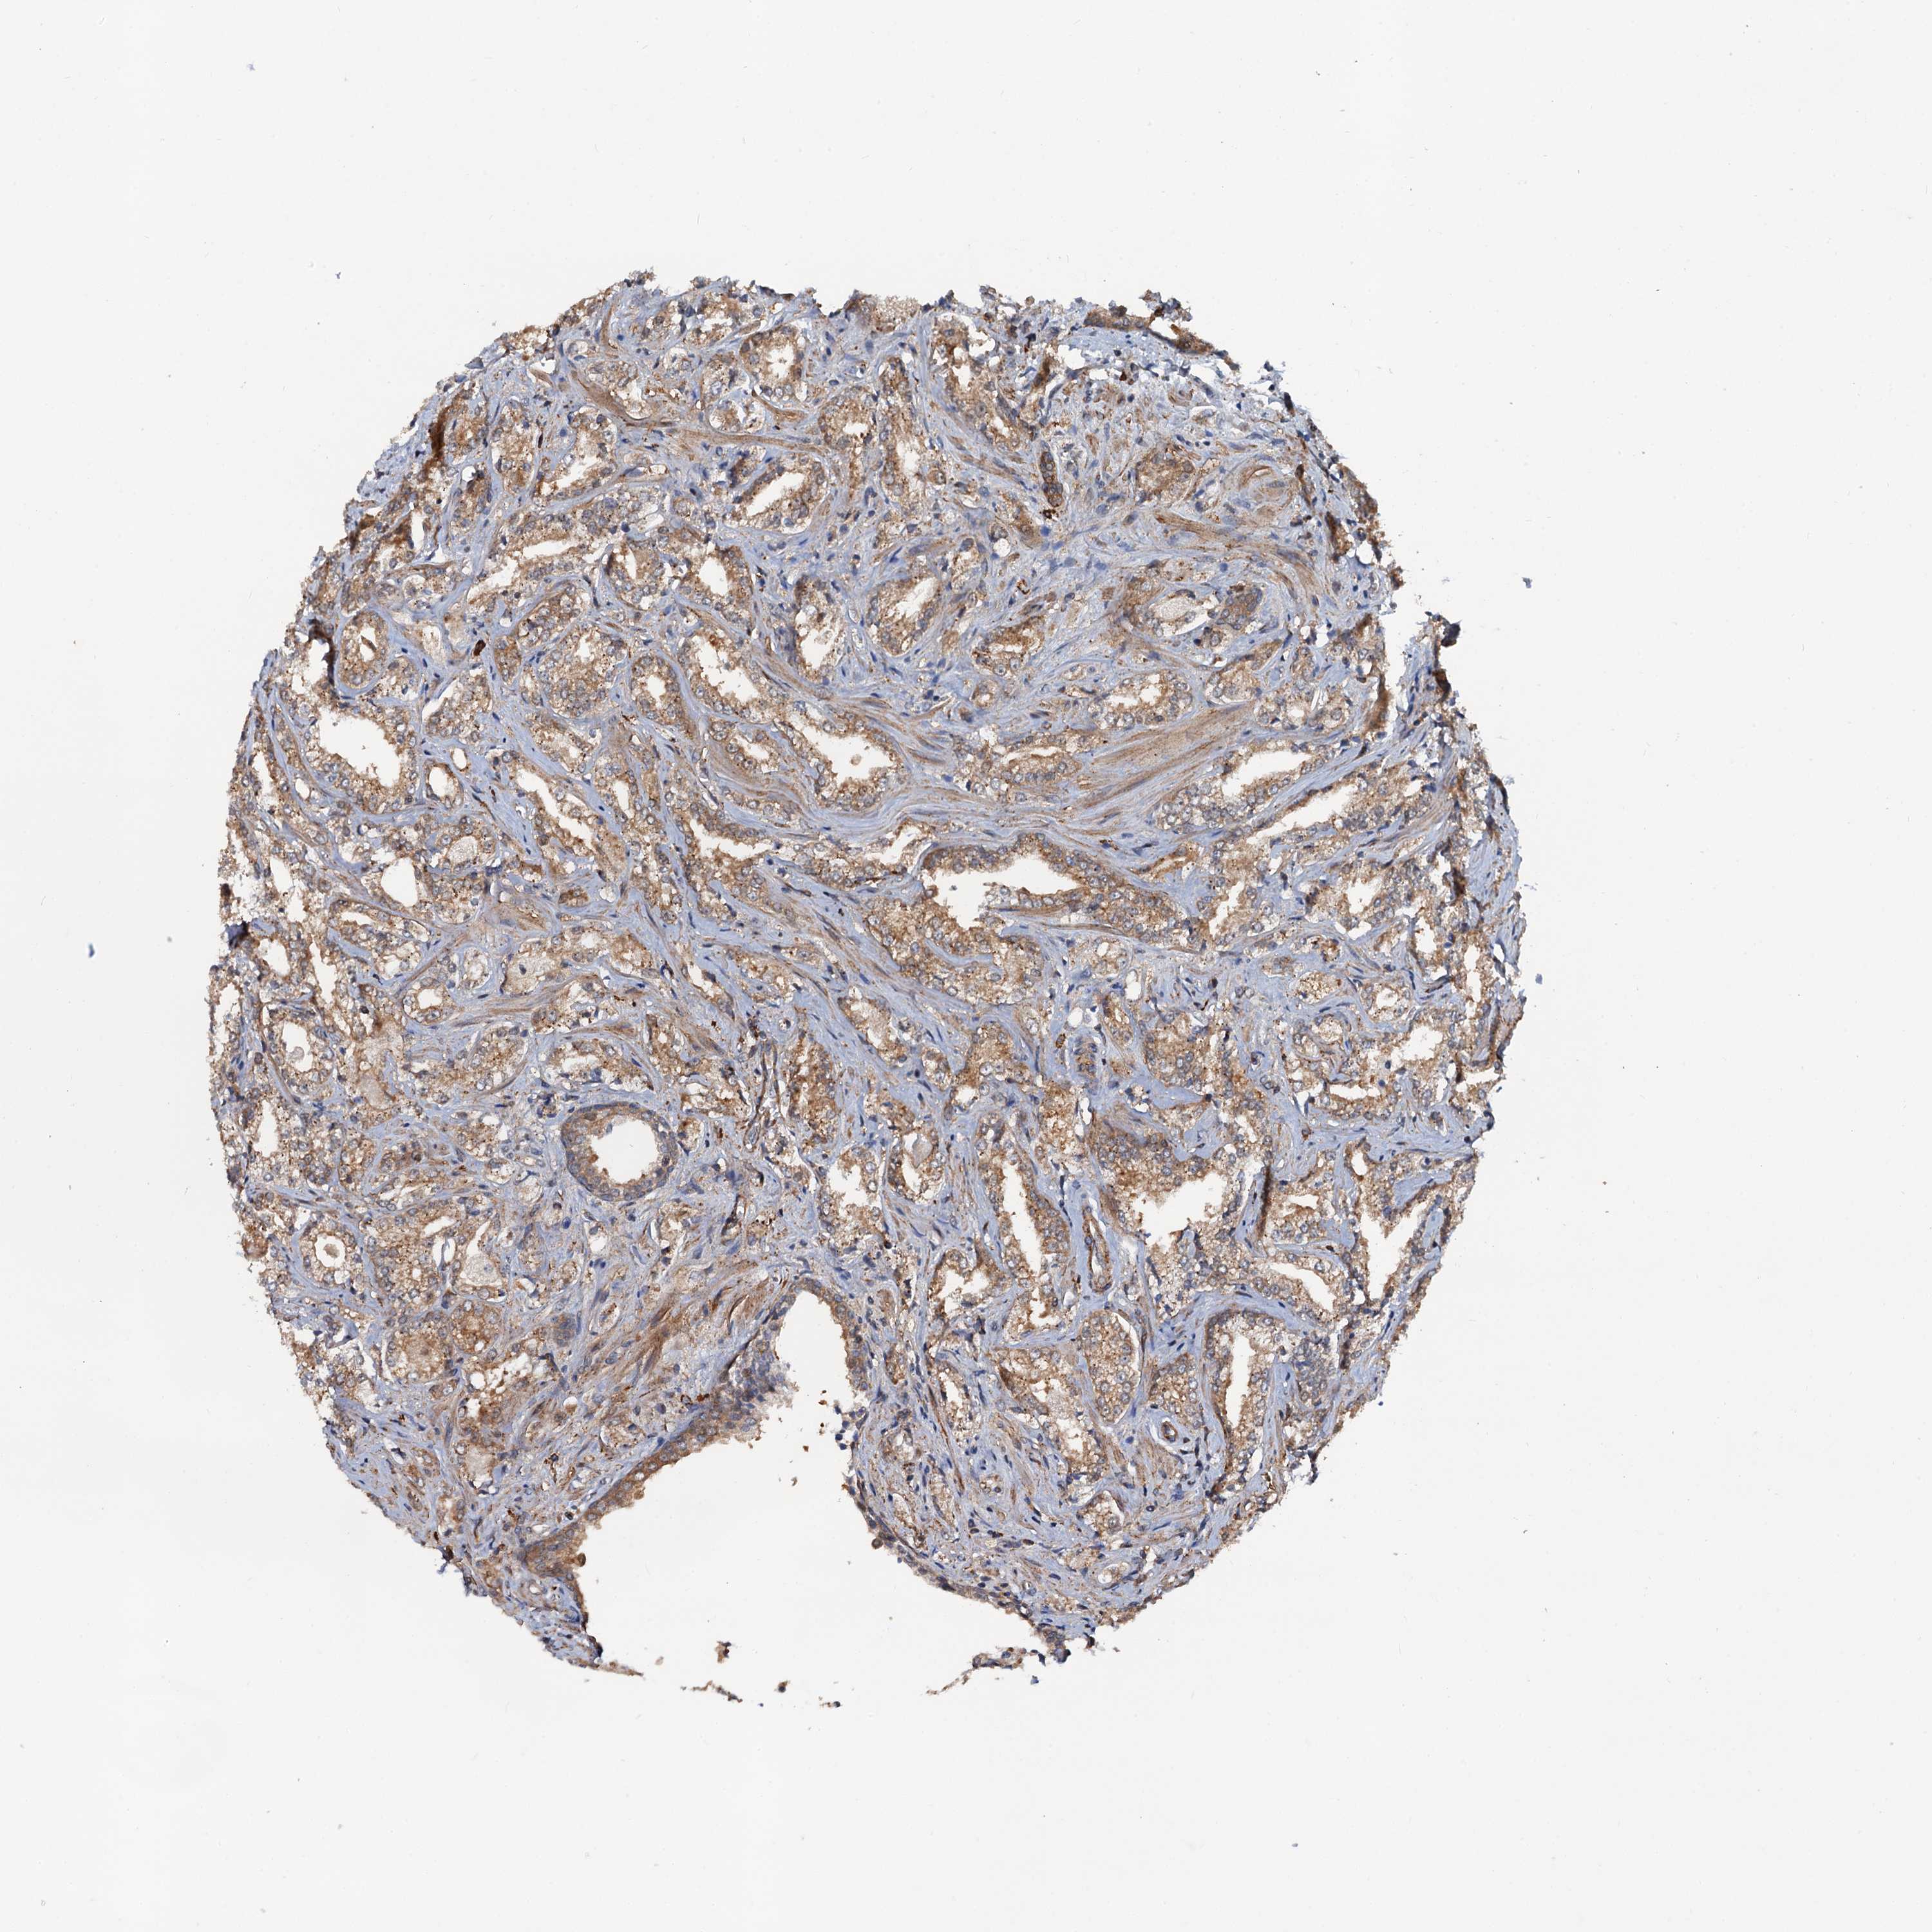

PROSTATE CANCER - Protein expressioni

A mouse-over function shows sample information and annotation data. Click on an image to view it in a full screen mode. Samples can be filtered based on level of antibody staining by selecting one or several of the following categories: high, medium, low and not detected. The assay and annotation is described here.

Note that samples used for immunohistochemistry by the Human Protein Atlas do not correspond to samples in the TCGA dataset.

Antibody stainingi

Antibody staining in the annotated cell types in the current human tissue is reported as not detected, low, medium, or high, based on conventional immunohistochemistry profiling in selected tissues. This score is based on the combination of the staining intensity and fraction of stained cells.

Each image is clickable and will lead to virtual microscopy that enables deeper exploration of all samples and also displays staining intensity scores, fraction scores and subcellular localization as well as patient and tissue information for each sample.

Antibody HPA039371

Antibody HPA040174

Staining

High

Medium

Low

Not detected

Intensity

Strong

Moderate

Weak

Negative

Quantity

>75%

75%-25%

<25%

None

Location

Nuclear

Cytoplasmic/membranous

Cytoplasmic/membranous,nuclear

Adenocarcinoma, NOS

Adenocarcinoma, High grade

Adenocarcinoma, Low grade